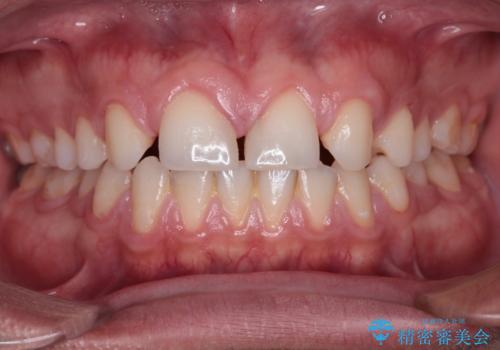

欠損して隙間のある前歯 オールセラミッククラウンで自然な口元に

- 歯の欠損による前歯のすきっ歯を気にして来院された患者様です。

矯正治療かオールセラミックか、治療の選択がありましたが、熟考の末オールセラミッククラウンにて補綴することとしました。